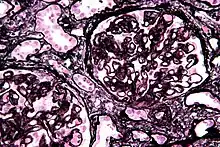

| Micrograph of diffuse proliferative lupus nephritis showing increased mesangial matrix and mesangial hypercellularity. Kidney biopsy. PAS stain. | |